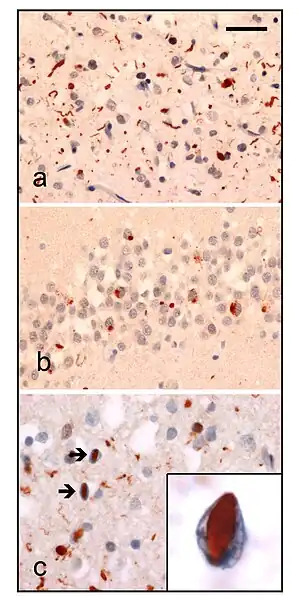

Neuropathologic analysis of brain tissue from FTLD-TDP patients. Ubiquitin immunohistochemistry in cases of familial FTLD-TDP demonstrates staining of (a) neurites and neuronal cytoplasmic inclusions in the superficial cerebral neocortex, (b) neuronal cytoplasmic inclusions in hippocampal dentate granule cells, and (c) neuronal intranuclear inclusions in the cerebral neocortex (arrows). Scale bar; (a) and (b) 40 μm, (c) 25 μm, insert 6 μm.

• Type A presents with many small neurites and neuronal cytoplasmic inclusion bodies in the upper (superficial) cortical layers. Bar-like neuronal intranuclear inclusions can also be seen they are fewer in number.

• Type B presents with many neuronal and glial cytoplasmic inclusions in both the upper (superficial) and lower (deep) cortical layers, and lower motor neurons. However neuronal intranuclear inclusions are rare or absent. This is often associated with ALS and C9ORF72 mutations (see next section).

• Type C presents many long neuritic profiles found in the superficial cortical laminae, very few or no neuronal cytoplasmic inclusions, neuronal intranuclear inclusions or glial cytoplasmic inclusions. This is often associated with semantic dementia.

• Type D presents with many neuronal intranuclear inclusions and dystrophic neurites, and an unusual absence of inclusions in the granule cell layer of the hippocampus. Type D is associated with VCP mutations.